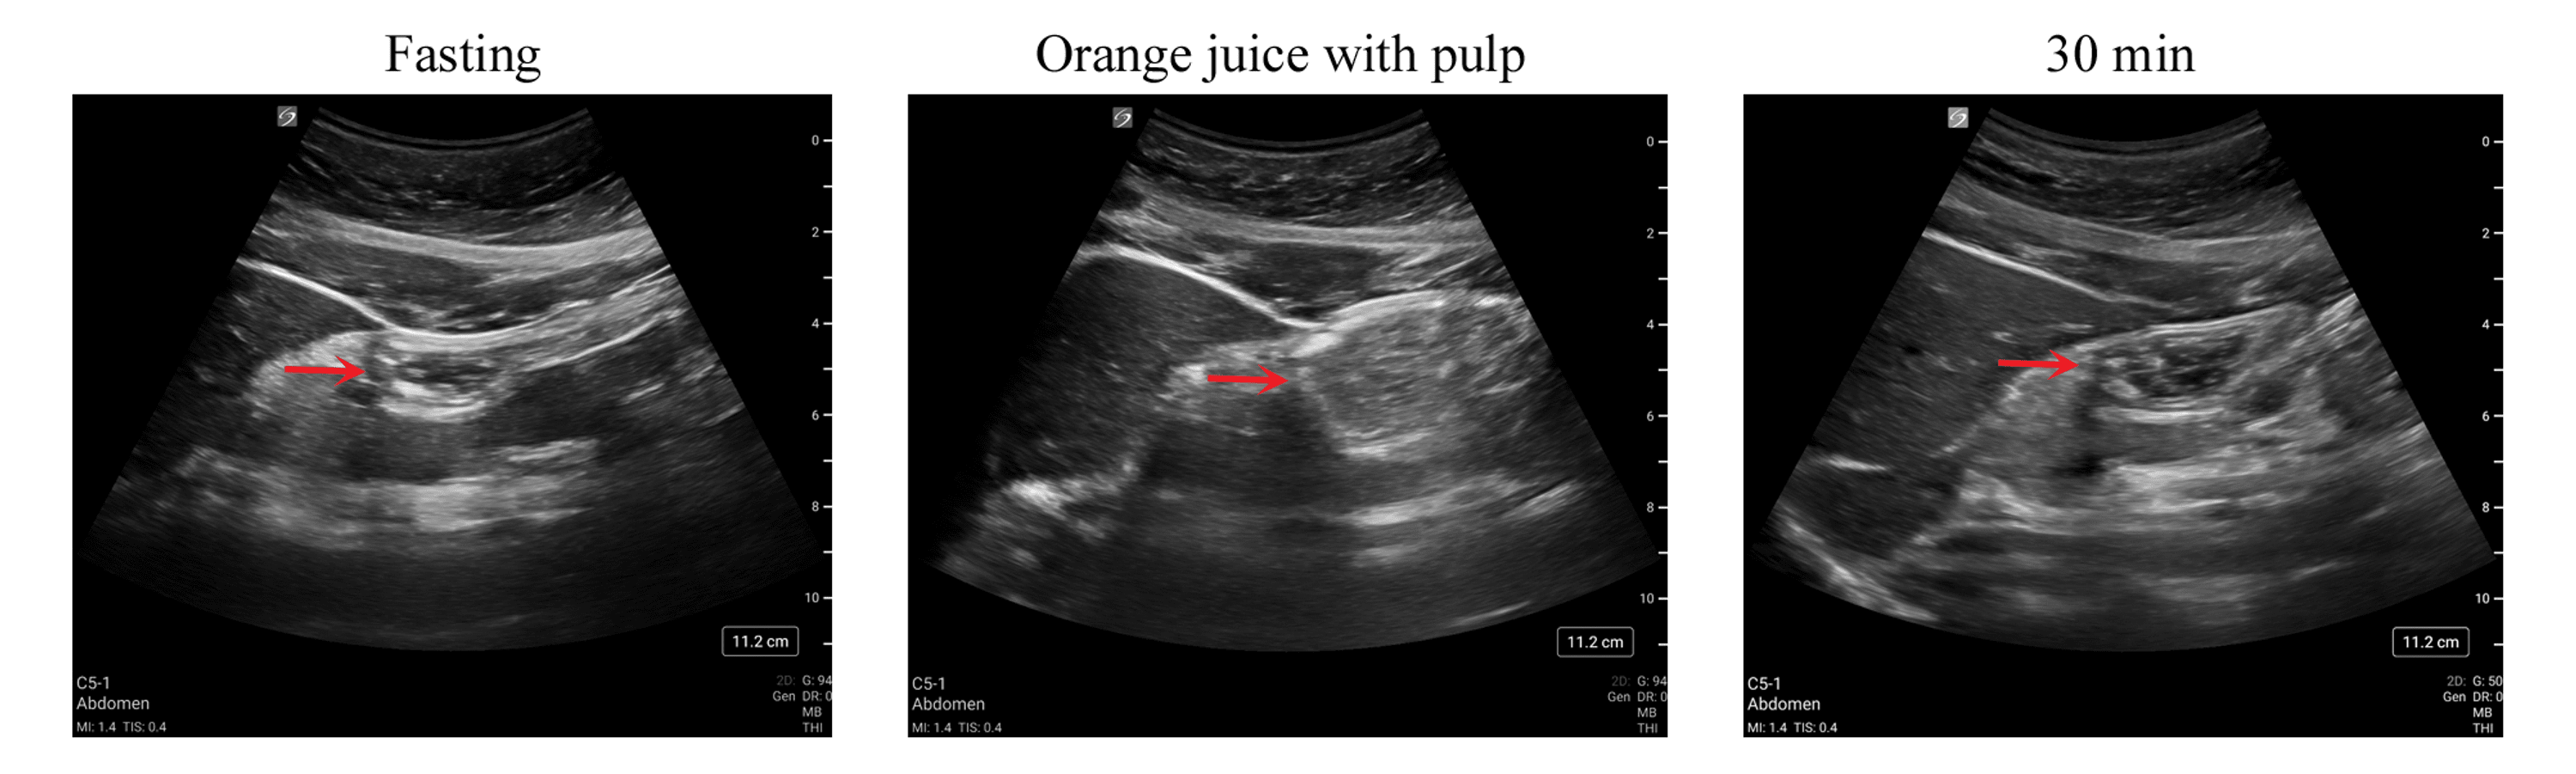

Gastric Emptying of Orange Juice With and Without Pulp A PointofCare Oranges And Gastric Find out which foods can help heal gastritis and prevent ulcers, and which ones to avoid. Learn which foods can make indigestion worse, such as dairy, acidic, fatty, fried, processed, and spicy foods. Learn how to manage gastritis symptoms with a diet that reduces acidity, fat, and irritants. A gastritis diet can help ease symptoms of gastric inflammation, including indigestion,. Oranges And Gastric.